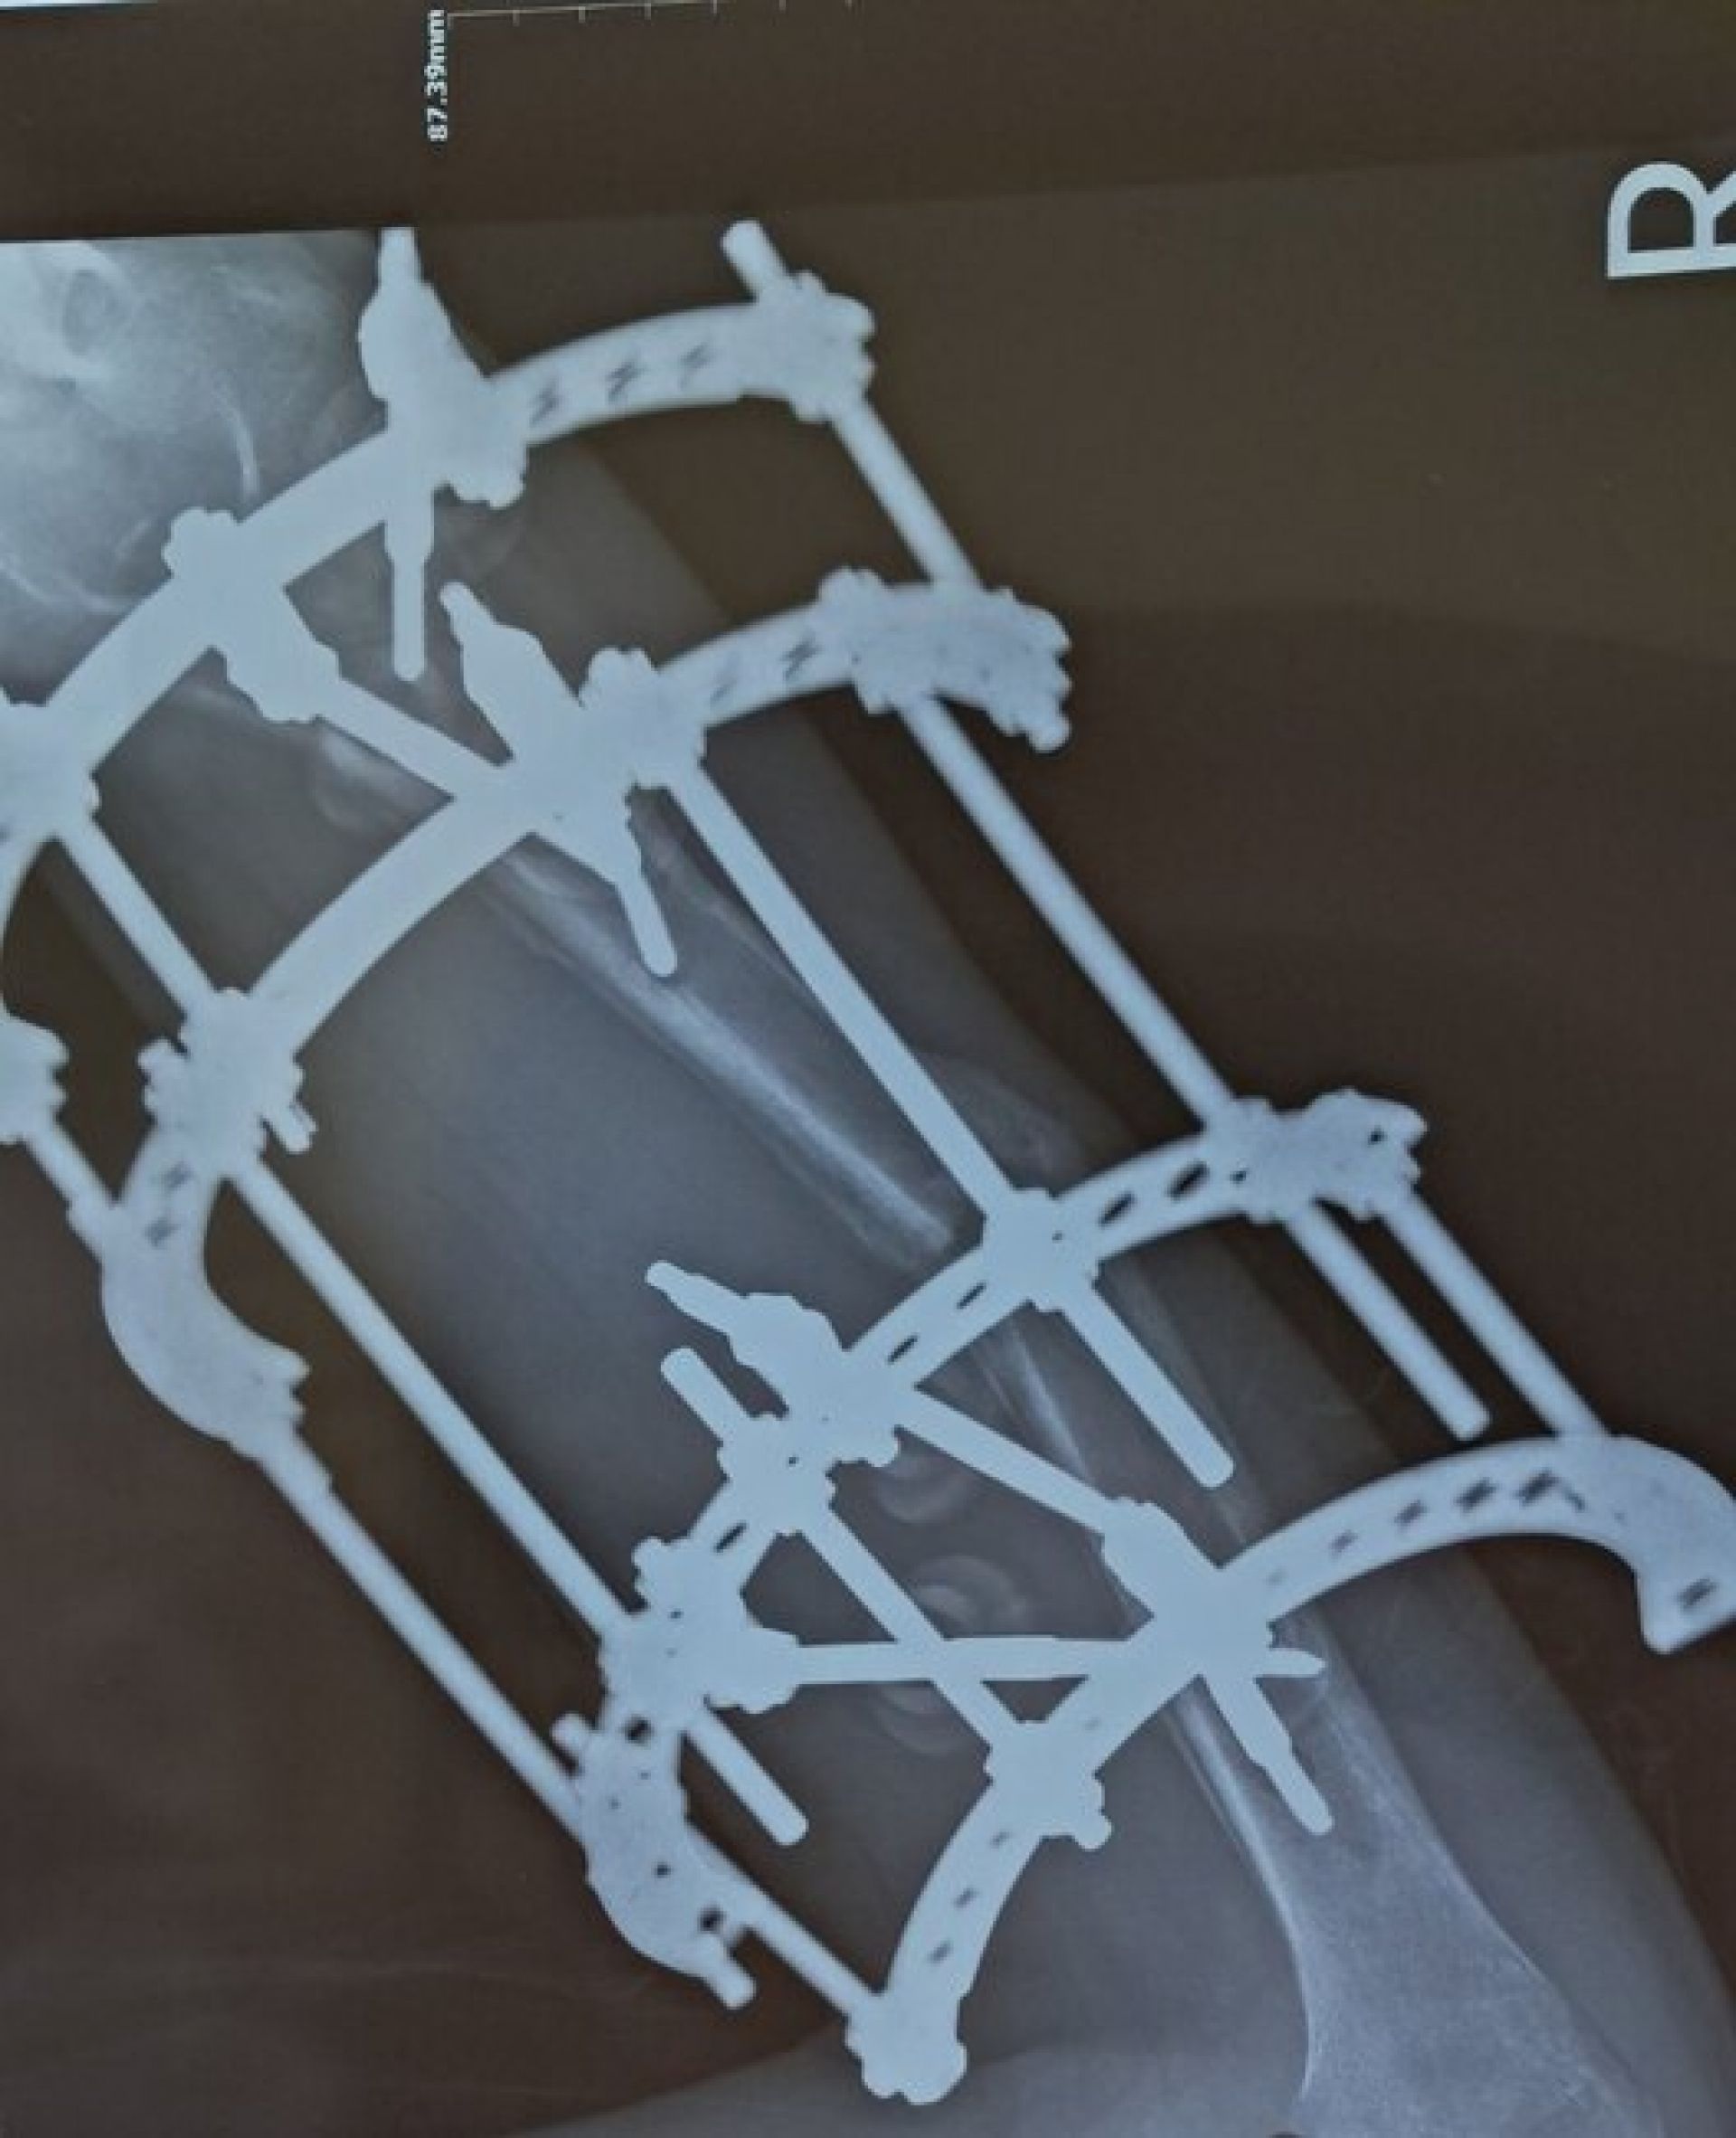

За шість місяців 2025 року до лікарні потрапило 38 дітей, постраждалих у ДТП. Лише за червень таких випадків було 12. Найпоширеніші травми — переломи кінцівок, черепно-мозкові ушкодження, травми хребта та політравми.